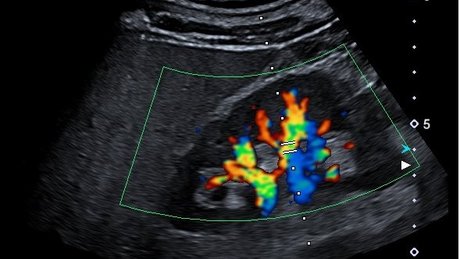

• Nierensonographie inklusive Duplexsonographie bei Verdacht auf Nierenarterienstenose und Konstrastmittel gestützter Nierenultraschall

• Ultraschall gestützte Nierenbiopsien

Zur diagnostischen Sicherung vieler Nierenerkrankung, insbesondere bei den Glomerulonephritiden, ist häufig die Gewinnung einer histologischen Probe aus einer der Nieren (Nierenbiopsie) nötig. Dieses Verfahren erfolgt mithilfe des Ultraschalls und in örtlicher Betäubung.